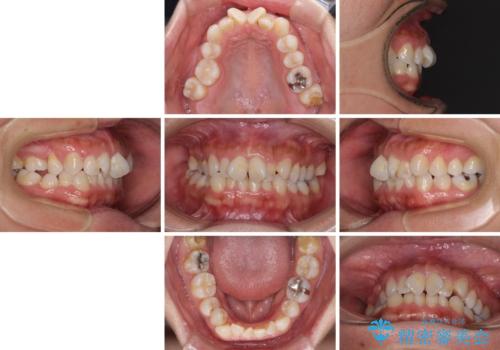

- 上下前歯のデコボコを気にして来院された患者様です。

右上と左下の小臼歯が1本ずつ欠損しており、奥歯の咬み合わせが乱れている状態でした。

バランスを取るために右下と左上の小臼歯を1本ずつ抜歯し、移動のための固定源としてアンカースクリューを利用してワイヤー装置による矯正治療を行うこととしました。

骨格的な左右差があり、上下正中をぴったり合わせることは難しく、奥歯の咬み合わせの調整にも時間がかかりましたが、きれいに整えることができました。